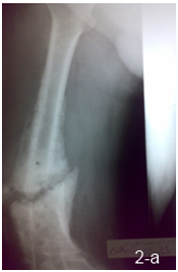

14 patients were operated by a 2 stage strategy including debridement at the fracture site through lateral approach with excision of all infected tissues and necrotic bone with no external fixation in the first session, then rest and parenteral antibiotic was given for 4 to 6 weeks and follow up with serial ESR & CRP were done before second session, 6 weeks after the first session; the second session was done through fixation by locked intra medullary nail with use of autogenous cancellous bone graft in patients with bone defects more than 2 cm (Figure 2 a, b).

Figure 2 a) Femoral infected non union after removal of implant in 1st stage. b) 2nd stage fixation by nail.